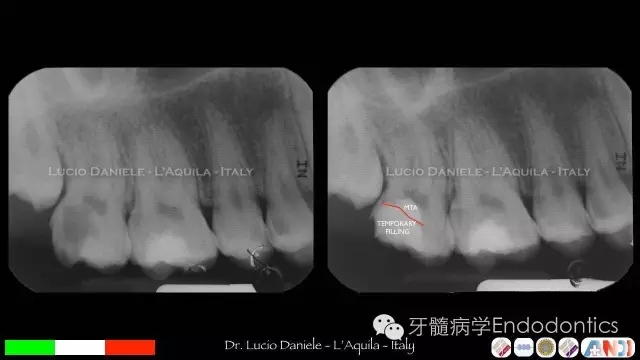

圖6.

圖7.隨訪1年、2年